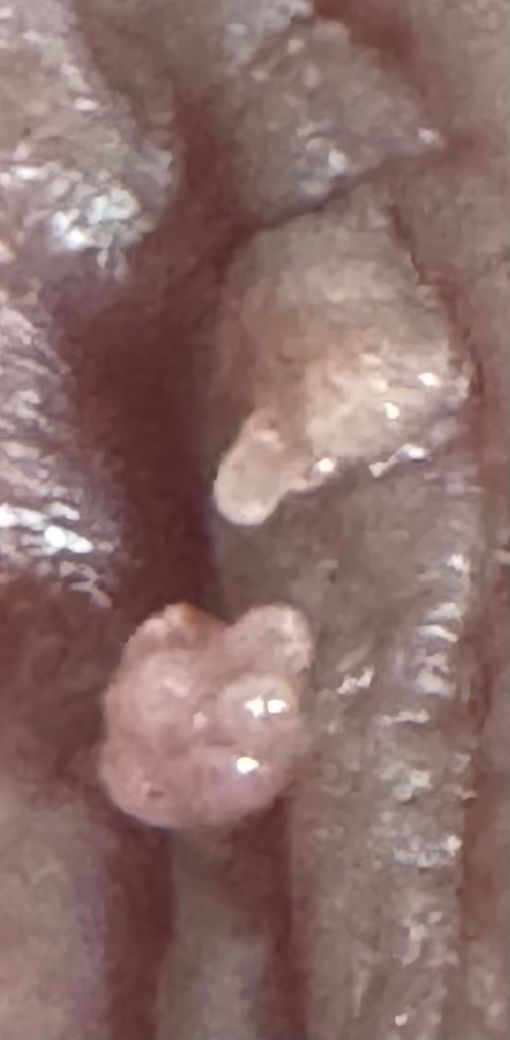

여자 생식기 돌기 여성 곤지름 인가요?

어느날 갑자기 사마귀 같은게 생겼습니다 위치는 소음순? 클리옆에 있는 날개 윗쪽입니다

산부인과를 가보니 곤지름은 아니라고 하는데 아무리 봐도 곤지름 같고 진료를 꼼꼼하게 안하신거 같아요 다시 산부인과를 가봐야 할까요? 생긴지는 몇달 되었는데 두개정도 있고 번지지는 않았어요 크기는 쌀알 반정도 크기입니다

사진상으로 보기에 곤지름의 가능성이 있겠습니다만, 조직검사 등을 통하여 진단하는 것이 일반적입니다.

찝찝하여 제거 후 검사를 하고 싶으시다면, 산부인과에 다시 내원하시는 것을 권유드립니다.